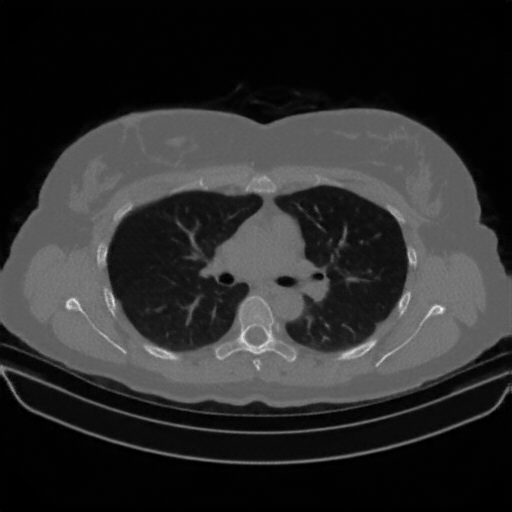

Original NATIVE CT scan (input)

Full window (WL 1023.5, WW 4095 β†’ Low βˆ’1024, High +3071)

Actual HU range: [-1024.0, 1296.0]

Lung window (WL -600, WW 1500 β†’ Low βˆ’1350, High +150)

Actual HU range: [-1024.0, 150.0]

Mediastinum window (WL 40, WW 400 β†’ Low βˆ’160, High +240)

Actual HU range: [-160.0, 240.0]